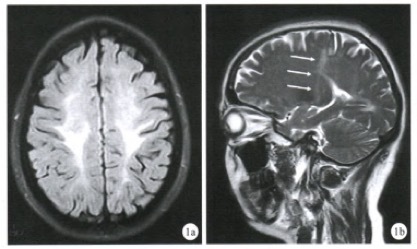

图 7 沿着脑室壁的白质高信号,形似「花环」

图 10 A~B:T2WI 和 FLAIR 可见双侧弥漫白质高信号,累及 U 形纤维,内囊和外囊,伴深部白质空泡化